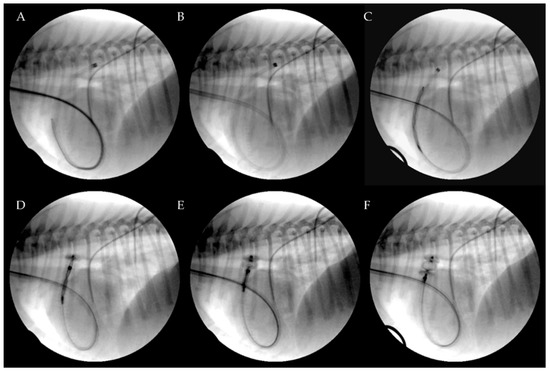

Premedication included methadone (0.2 mg/kg, intramuscularly [IM]). Anesthesia was induced with fentanyl (3 mcg/kg intravenously [IV]), midazolam (0.2 mg/kg IV) and propofol (3 mg/kg IV). An appropriate plane of anesthesia was maintained, with isoflurane and oxygen delivered via a precision vaporizer and a non-rebreathing circuit. For the procedure, all dogs were placed in left lateral recumbency on the fluoroscopy table. The right jugular vein was surgically isolated by the cut down technique and a 7 or an 8 Fr introducer vascular sheath (PINNACLE® R/O II HIFLO Introducer Sheath 7 Fr × 4 cm × 0.038″ or PINNACLE® PERIPHERAL Introducer Sheath 7 Fr/8 Fr × 10 cm × 0.035″ Terumo Interventional Systems, Tokyo, Japan; Super Sheath™ Introducer Sheath 8 Fr/9 Fr × 11 cm × 0.038″, distributed by Boston Scientific Corporation, Natick, MA, USA, manufactured by Togo Medikit Co., Ltd., Hyūga, Tokyo, Japan) was placed into the right jugular vein. A 4 Fr Berenstein guiding catheter (distributed by Infiniti Medical, Huddersfield, UK and manufactured by Abbott Medical, Plymouth, MN, USA) or 5 Fr multipurpose catheter (Beacon Tip 5 Fr × 0.038″ × 100 cm, Cook Medical Inc, Bloomington, IN, USA) was then inserted into the jugular vein along with a preplaced straight tip soft guidewire (0.035″ Terumo Glidewire, 0.035″ × 150 cm, Straight). It was passed through the right ventricle, the pulmonary artery and the PDA in a retrograde manner until the tip of the guiding catheter or multipurpose catheter was located in the descending aorta under fluoroscopy guidance. After removing the guidewire, an angiographic study using iohexol was performed showing the location and the morphology of the PDA. Following angiography, a Cook Rosen PTFE Curved Wire Guide 0.035″ × 145 cm was advanced into the descending aorta and the Berenstein guiding catheter or multipurpose catheter was removed. Based on the chosen AVP II size, a 5.5 Fr to 6 Fr × 40 cm guiding sheath (Flexor Balkin, Cook Medical Inc, Bloomington, IN, USA) was advanced over the guidewire into the descending aorta (Figure 2) acting as delivering catheter, and the guidewire was subsequently removed.

The device was introduced into the Balkin guiding sheath through the Check-Flo Valve and then advanced carefully until the distal disc was expanded into the descending aorta near the ductus. The partially-deployed AVP II, the attached delivery cable and the guiding sheath were gently pulled back simultaneously, until the distal disc engaged the aortic ostium of the PDA. The guiding sheath then was retracted while slightly pushing the delivery wire, allowing the central component of the device to expand into the PDA ampulla (Figure 3).

Figure 3. Transjugular patent ductus arteriosus occlusion using the Amplatzer Vascular Plug II. The PDA was crossed retrograde using a straight soft guidewire advanced into the descending aorta through the right ventricle and the pulmonary artery on a 5 Fr multipurpose catheter. The soft guidewire was replaced by a standard Cook Rosen PTFE curved guidewire used to position the tip of the Flexor Balkin guiding sheath into the aorta and was then removed (A). The Flexor Balkin guiding sheath is in correct position (B). The device was introduced into the Balkin guiding sheath (C). The Amplatzer Vascular Plug II was advanced (C), partially (D) and fully extruded (E) and occluding the PDA (F).